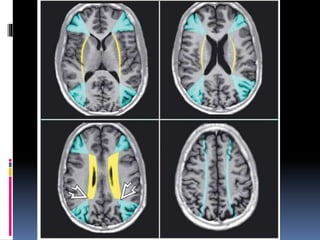

WATERSHED INFARCTS

 Occur at the junction between the two nonanastamosing

distal arterial distributions

External watershed zones:

 Frontal cortex( b/w ACA & PCA junction)

 Parietoocipital cortex ( b/w MCA & PCA junction)

 Paramedian subcortical white matter near the vertex.

Internal watershed zones:

 Junction b/w penetrating branches & major cerebral

vessels.

WATERSHED INFARCTS  Occurat the junction between the two nonanastamosing distal arterial distributions External watershed zones:  Frontal cortex( b/w ACA & PCA junction)  Parietoocipital cortex ( b/w MCA & PCA junction)  Paramedian subcortical white matter near the vertex. Internal watershed zones:  Junction b/w penetrating branches & major cerebral vessels.

• 49.

Axial FLAIR scandemonstrates typical findings of bilateral external (cortical) watershed infarcts

• 50.

Nearly symmetric confluentand punctate deep white matter hyperintensities are seen above and behind the lateral ventricles . FLAIR scan just above the previous image shows distinct bilateral rosary-like white matter hyperintensities